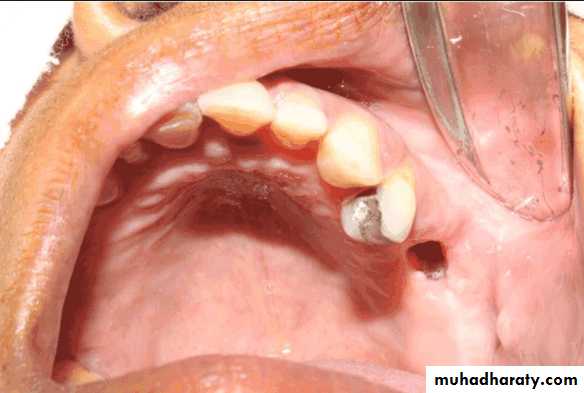

• Problems requiring immediate attention:

• Large carious lesions: excavation, temporary restorations• Ill-fitting dentures: adjustment or temporary relining to eliminate discomfort & allow recovery of the damaged tissues.